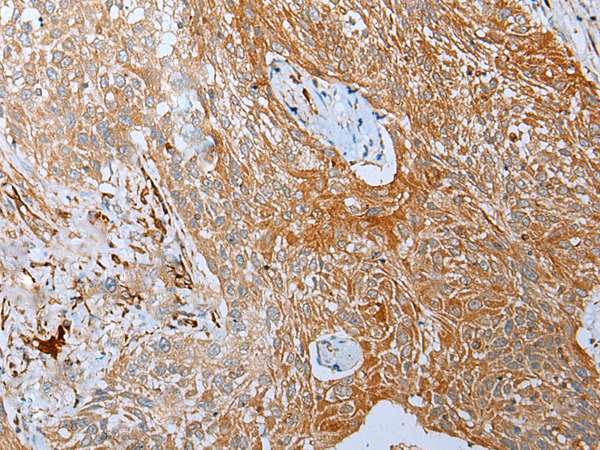

IHC positive control: |

Human gastric cancer and human lung cancer |

IHC Recommend dilution: |

25-100 |